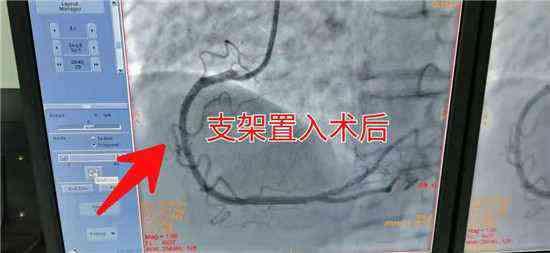

近日,新邵縣人民醫(yī)院急診科接來一位85歲,胸痛、胸悶的老人,根據(jù)其癥狀及臨床表現(xiàn),醫(yī)生初步診斷為急性心肌梗死。病情就是軍令,迅速為患者完成各項檢查,第一時間送入介入科搶救。五分鐘內(nèi)各路人員迅速到位,迅速給患者擺體位、上監(jiān)護(hù)、消毒、鋪巾、穿刺、送管、造影一氣呵成。冠脈造影顯示患者為急性下壁心肌梗死,需緊急為患者置入支架 打通血管。時間就是心??!關(guān)鍵在此一搏,在家屬的積極配合下,迅速談話簽字,一切準(zhǔn)備就緒。

介入醫(yī)生輕舞導(dǎo)絲、細(xì)捻導(dǎo)管、聚精會神,半小時內(nèi)一枚冠脈支架有條不紊的送到了老人病變血管部位,為患者冠脈血管架起了一座圓形橋梁。堵塞的血管道路通了,心肌得到了有效的灌溉,血液歡快的流淌著,唱著生命的歌。